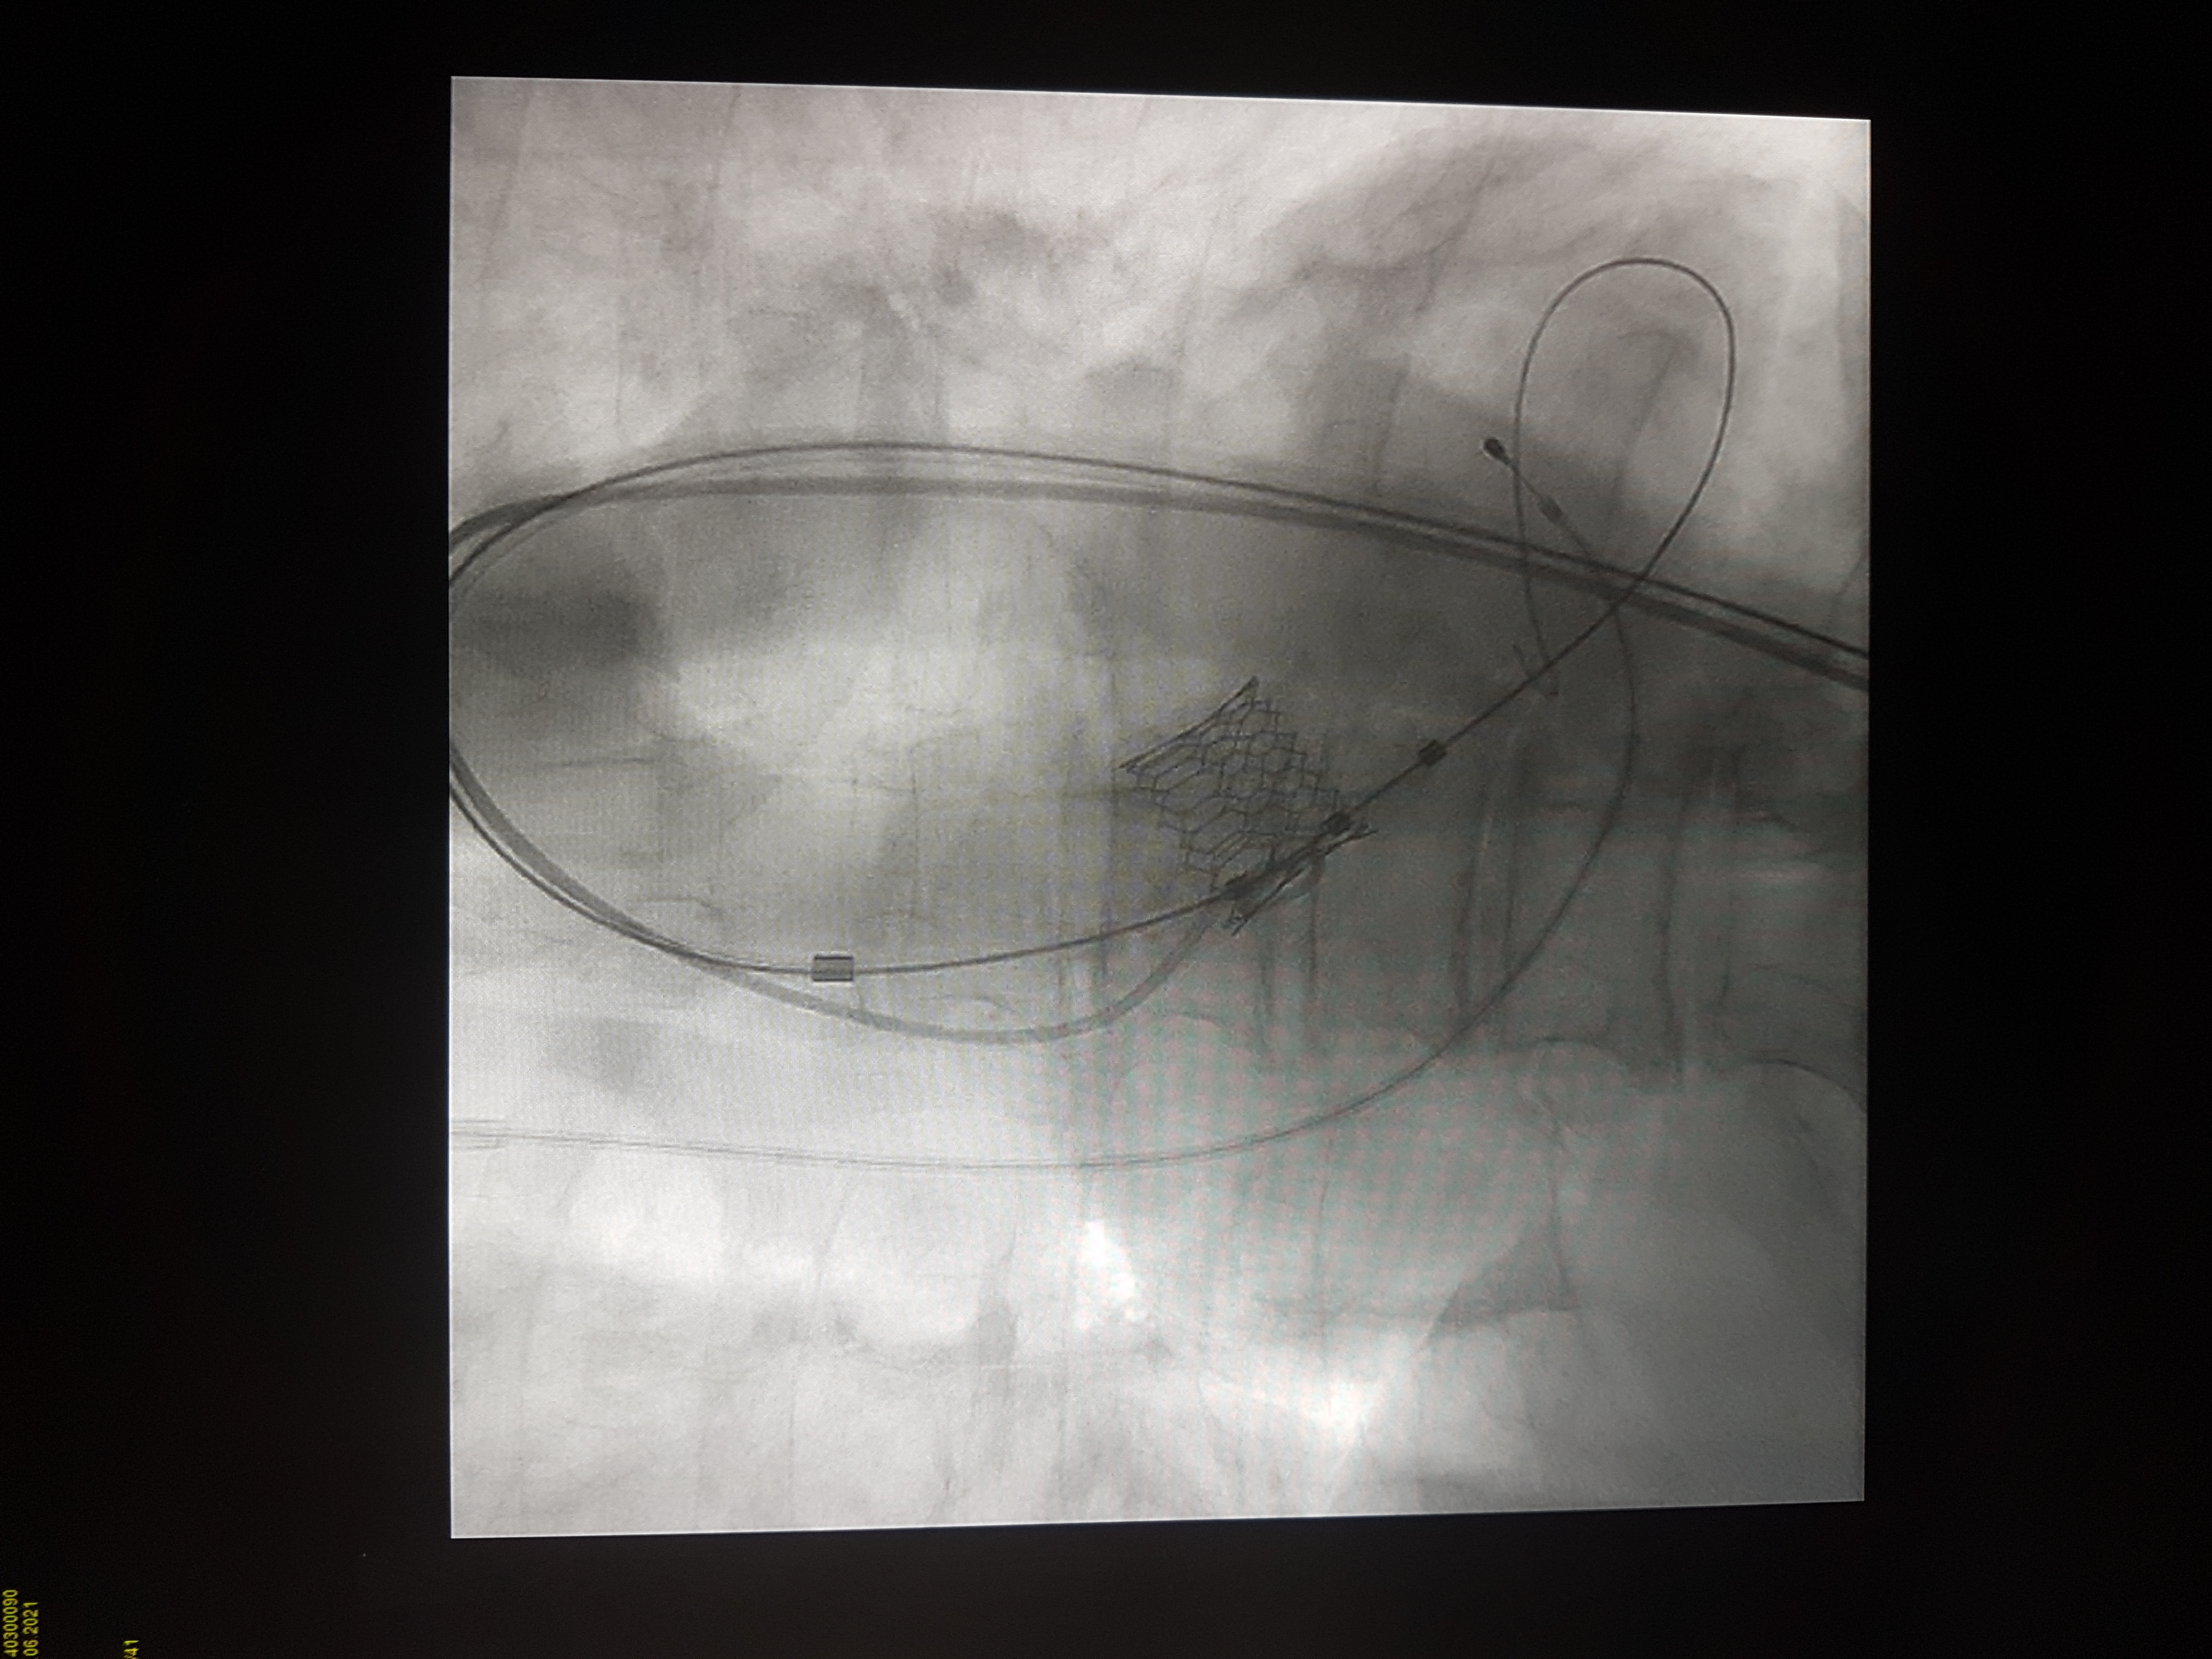

V Splošni bolnišnici Celje so prejšnji teden začeli izvajanje priznane klinične metode zdravljenja z zožitvijo aortne zaklopke – TAVI (Transcatheter Aortic Valve Implantation).

Prva posega so izvedli pod mentorstvom vodje katetrskega laboratorija UKC Ljubljana prof. dr. Matjaža Bunca in srčnega kirurga prim. Gorazda Koširja iz UKC Maribor. Bila sta uspešna, pacienta pa sta tri dni po posegu lahko zapustila bolnišnico.

Perkutana implantacija aortnih zaklopk (TAVI) ali vstavitev srčnih zaklopk skozi žilo na nogi je priznana klinična metoda zdravljenja bolnikov s pomembno zožitvijo aortne zaklopke.

Gre za poseg, pri katerem skozi eno od večjih arterij na stegnu uvedejo umetno biološko aortno zaklopko in jo po žilah vodijo do srca in mesta vstavitve. Njena bistvena prednost je minimalna invazivnost posega v telo. Drugi, kirurški načini namreč zahtevajo odprtje prsnega koša, zunajtelesni obtok in dolgotrajno splošno anestezijo.